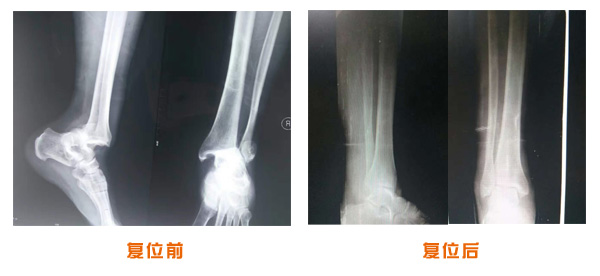

復(fù)位前后對(duì)比

肘關(guān)節(jié)脫位骨折治療前后對(duì)比